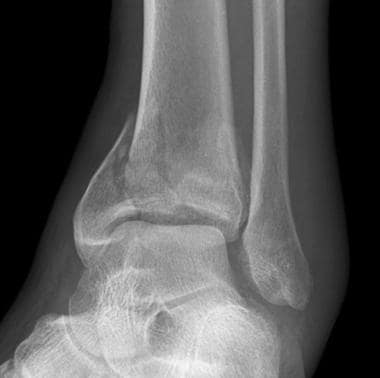

Diagnosis

With an ankle injury it is essential to rule out anything more serious, such as an anke fracture and this can be ruled out quickly. It is a highly sensitive and specific test and if negative, it is highly likely you do not have an ankle fracture. It is also important to rule out a syndesmosis injury, also known as a ‘high ankle sprain’.